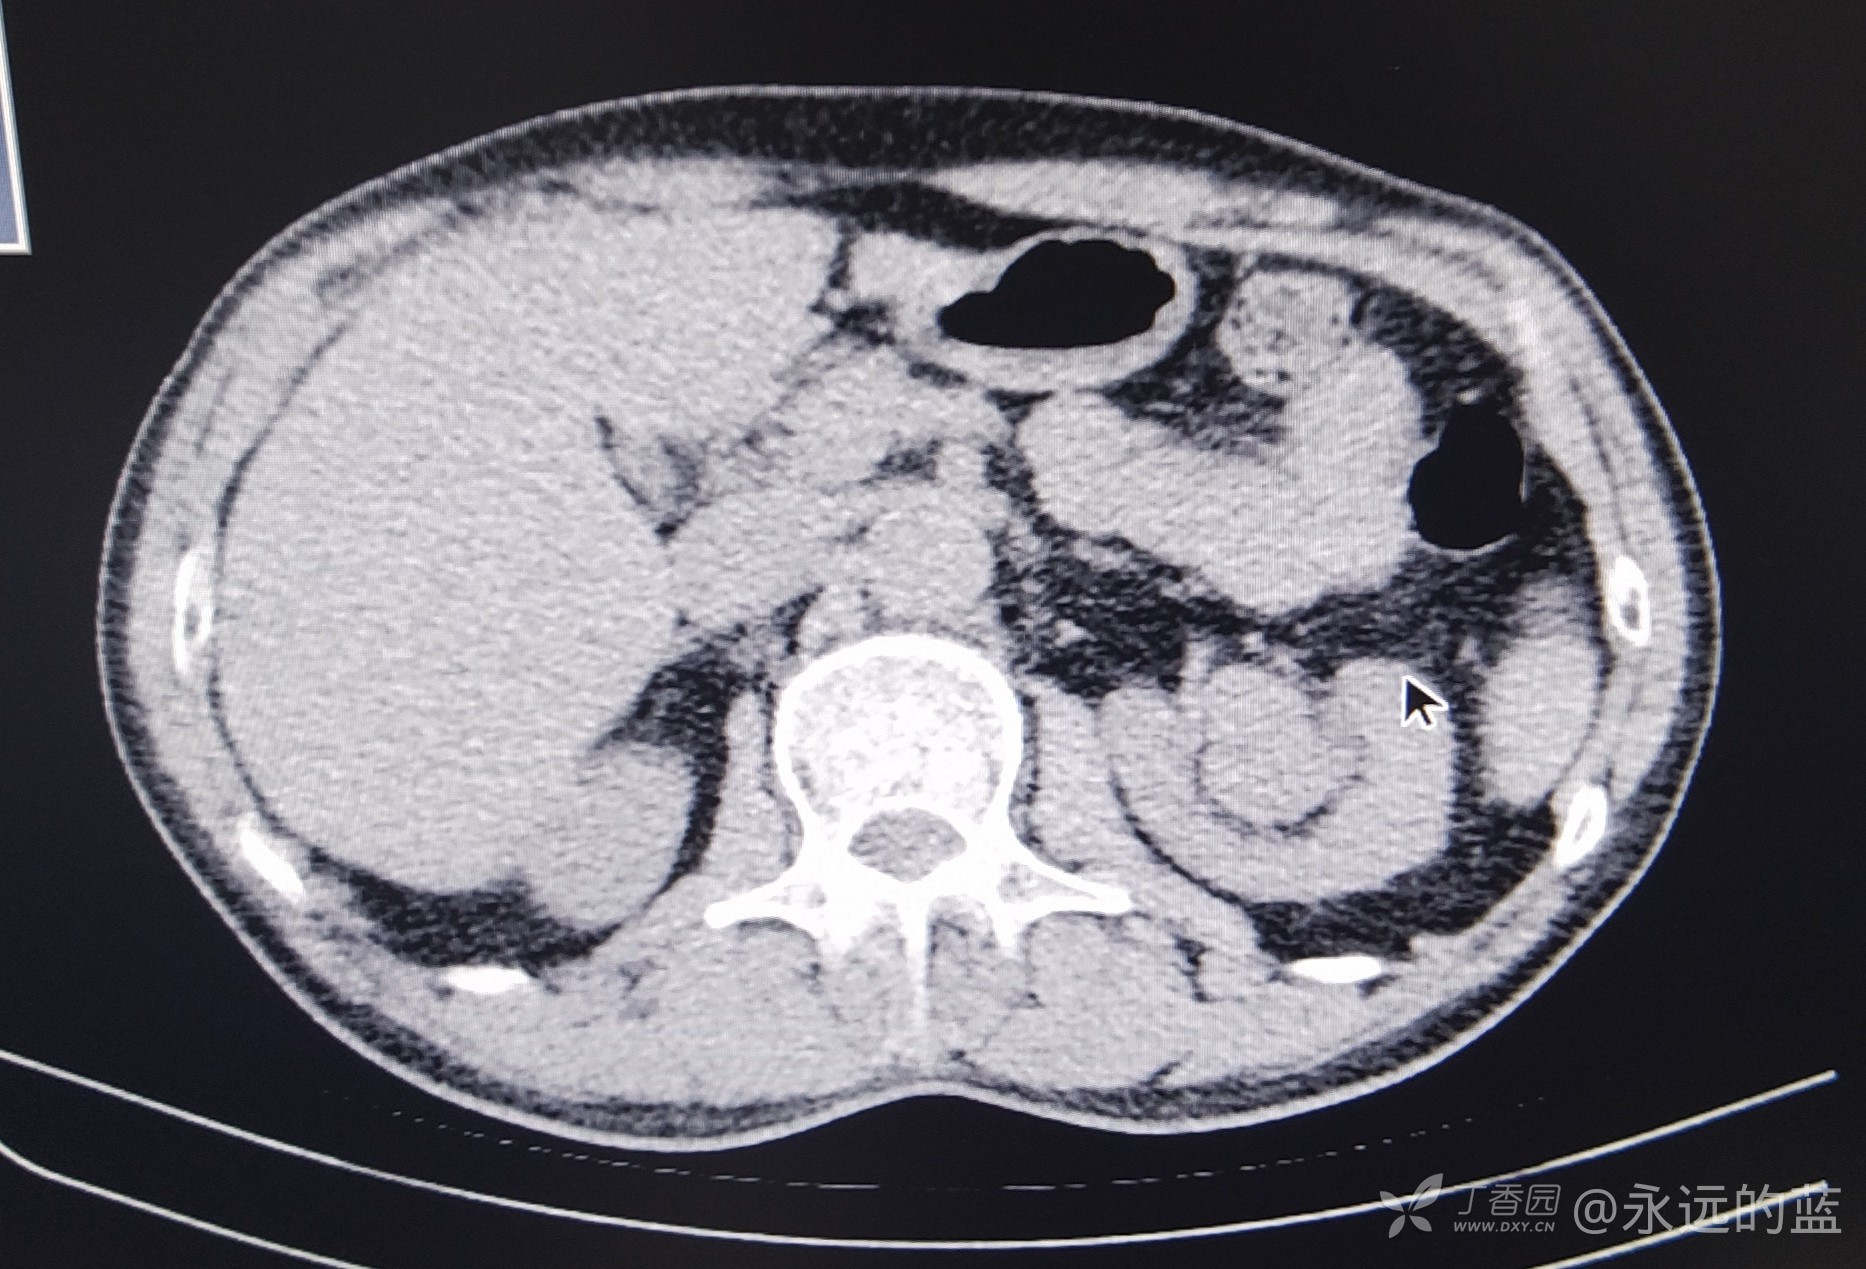

病例左肾窦内占位彩超与CT对比

男,58岁,体检发现左肾窦内可见高回声光团,患者自诉无血尿与不适,患者术后病理为肾癌